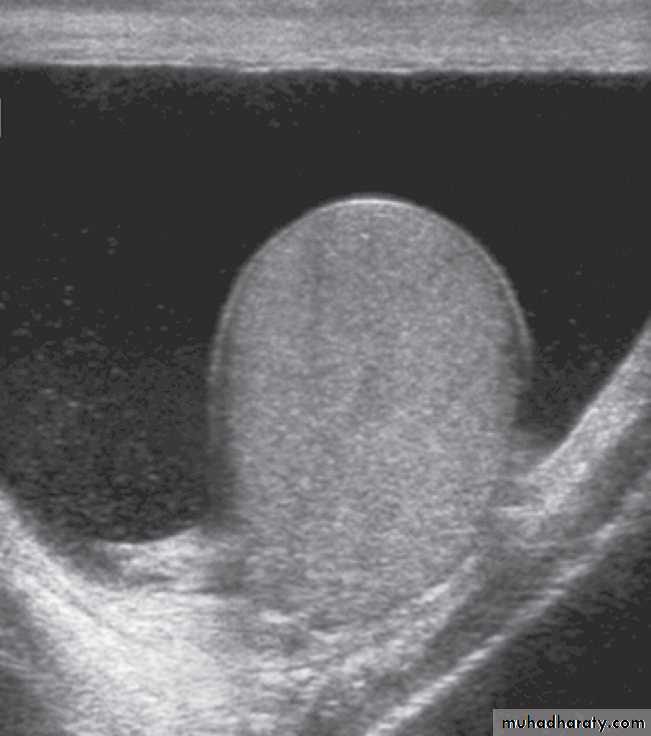

The scrotal contents are usually imaged with ultrasound, but MRI is occasionally used. The two main indications for scrotal ultrasound are 1.Scrotal swelling 2. Scrotal pain.In patients with scrotal swelling, it is essential to differentiate between an intratesticular cause, such as suspected testicular tumour, and an extratesticular cause, such as varicocele, hydrocele or infection (such as epididymitis or epididymo-orchitis) .

Doppler ultrasound can be used for patients with acute testicular pain and/or swelling to distinguish between testicular torsion, in which testicular perfusion is dramatically decreased, and acute epididymitis/orchitis, in which testicular perfusion is normal or increased.

Magnetic resonance imaging can produce highly detailed images of the scrotal contents but is only used in rare cases where ultrasound does not provide sufficient information.